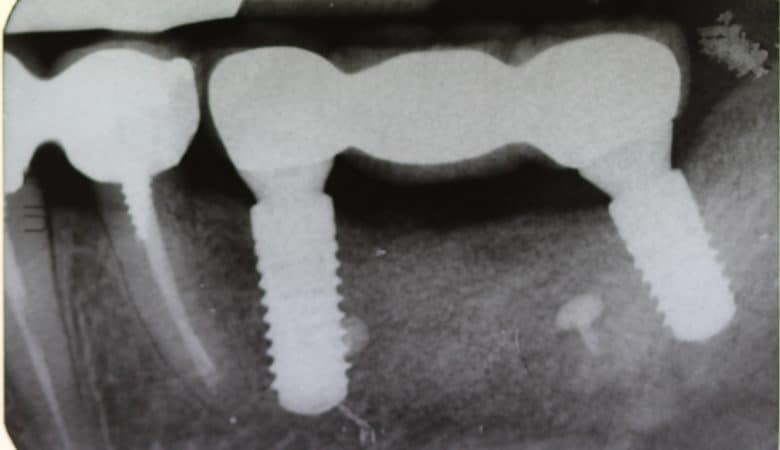

Material: Bio-Oss, Bio-Gide

Technique: Sinus Lift, Horizontal GBR

In female patient 51 years old, ASA 1 with tetracycline teeth pigmentation, 1.5 implant placement with simultaneous lateral sinus lift and horizontal bone regeneration sausage technique. At the same time 2.4 implant placement. Dott. Luca Corneli www.studiocorneli.com…